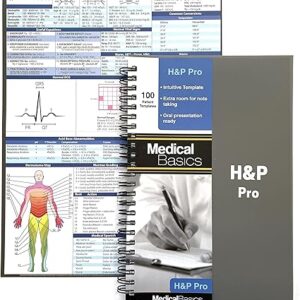

Diş İzi Alçı Kiti, doğru diş izleri almak için yeniden kullanılabilir diş tutucular ve aletler içerir. Birinci sınıf kaliteli malzemelerden üretilen bu kit, diş hekimleri, diş hekimliği öğrencileri ve eğitim amaçlı kullanım için idealdir ve hassas ve güvenilir sonuçlar sağlar.